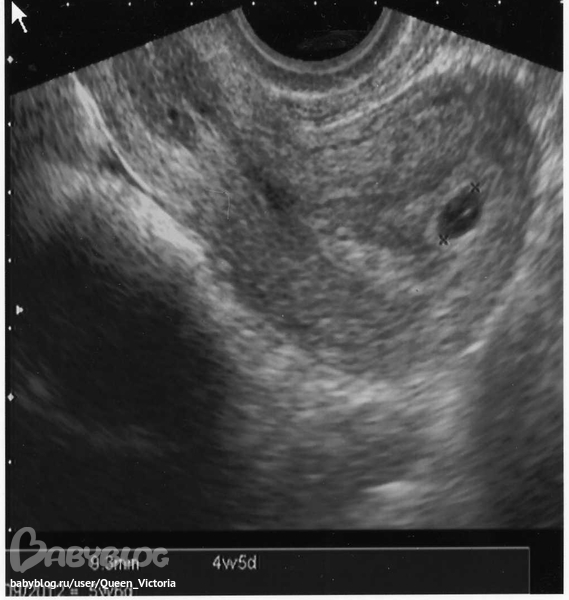

А вот и малыш

Врач сказала, что всё хорошо. Вышла я оттуда счастливая и довольная!!!!! Листок с результатами я получила только на выходе и поэтому расспросить о их значении не удалось..(

Вот что я потом там увидела:

КТР 1,9 мм

ВДПЯ 9,3 мм

Жёлтое тело в правом яичнике

И ещё надпись - гиперэхогенный венчик.

Дома как всегда залезла в инет, чтобы проверить в норме ли это и расстроилась(((

Перерыла несколько сайтов про соответствие КТР и недели Б. Пишут, что на моём сроке КТР должен быть 3-5 мм. У меня же 1,9.... Я не понимаю. Это нормально??? Или может врач ошибся.. И что такое гиперэхогенный венчик?